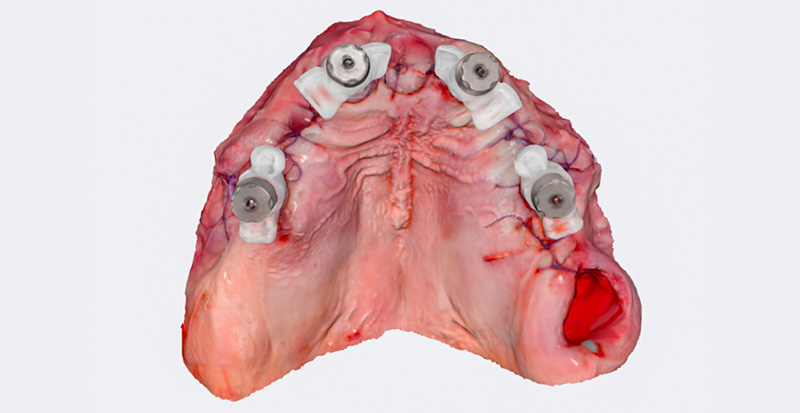

Immédiatement après la suture, des piliers de type « Scan-Transfer » de l’entreprise IPD, ont été placés sur les piliers « Multi-unit » (IPD propose des piliers « multi-unit » pour 25 marques d’implants dentaires et 80 plateformes différentes). Ceux-ci permettent une numérisation précise à l’aide d’un scanner intra-oral, selon un protocole spécifique qui évite toute distorsion de l’empreinte dans les zones édentées.

Le scan post-opératoire du maxillaire supérieur avec les « Scan-Transfers » a été réalisé dans un dossier séparé, indépendamment du scan préopératoire, et les deux ont ensuite été superposés au laboratoire. Le scan a été effectué avec un scanner intra-oral Medit i700, et le matching des empreintes a été réalisé dans le logiciel Exocad en se basant sur les zones fixes du palais et des tubercules du maxillaire.

Fig. 06 : Image du scan avec les Scan-Transfers IPD en place.